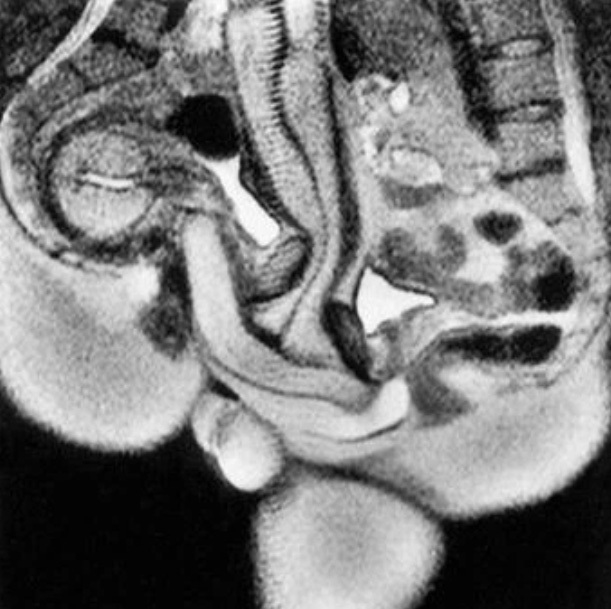

네덜란드 연구팀은 이 엠알아이를 통해 남성의 음경 모양이 기존의 생각과는 다르게 부메랑 모양이 된다는 것을 발견했다. 또 여자가 성적 흥분을 한다고 해서 자궁의 크기가 늘어나는 것이 아닌 것도 밝혔다.